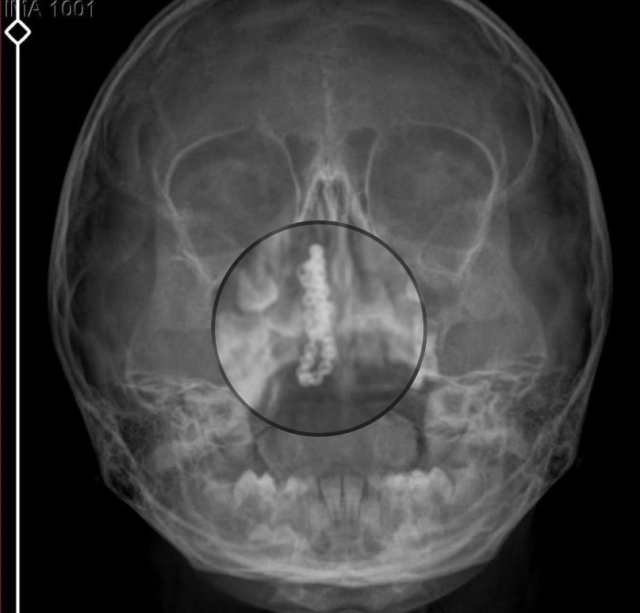

Devlet hastanesindeki doktorun incelemesi ve kapsamlı röntgen çekilmesi sonrası Polen'in burnunda metal cisim olduğu fark edildi. 2 yıldır burunda kaldığı değerlendirilip, küçük top şeklinde tırnak makası zinciri olduğu belirlenen cisim, başarılı ameliyatla çıkarıldı. Bir süre tedavisi sürdürülen Polen, sağlığına kavuşunca taburcu edildi. Özel hastane yetkilileri, konuyla ilgili açıklama yapmazken; aile suç duyurusunda bulunacaklarını söyledi.

Kızının burnundan sürekli siyah renkte akıntı olduğunu anlatan Gökhan Tekin, "Çocuğumun burnundan kanama ile sürekli siyah akıntı geliyordu. Özel hastaneye götürdüm. Özel hastanede film çekildi, hiçbir bulguya rastlanılmadığı söylendi. O siyah leke de enfeksiyona dayalı olan bir şey olduğu bize söylendi. Eve geldik, akıntı sürmesi üzerine bu kez devlet hastanesine başvurduk. Burunda metal zinciri fark ettiler. Böyle bir ihmalkarlık olabilir mi? Özel hastaneye gidiyoruz, paramızla rezil oluyoruz. Zincir, 2 yıldır burnunda ve devletimizin hastanesinde iyi bir doktorumuz zinciri ortaya çıkarıyor, kızım ölümden dönüyor. Ben sonuna kadar bu işin peşini bırakmayacağım. Sonuna kadar hukuk mücadelesi vereceğim. Bu da diğer hastalarımıza ibret olsun. İşte, bakın koca bir zincir. 'Bulguya rastlanılmadı' deniliyor" dedi.

Kızının ameliyat sonrası durumunun iyi olduğunu söyleyen Tekin, "İnanır mısınız bize 'Evde soba mı yanıyor? Acaba kömür isten dolayı mıdır bu?' dendi. Böyle bir şey olabilir mi? Ameliyattan çıkan parmağım kadar zincir. Devlet hastanesindeki doktor da 'Bu nasıl gözden kaçılabilir? Böyle bir pozisyon nasıl görülmeyebilir?' yorumunda bulundu. Allah'a şükür olsun atlattık. Şu anda durumu, vaziyeti iyidir. Ben şuna inanıyorum doktor da bir şans işidir. Bakın paramızla özele gideriz ya hani bizde, daha iyi ilgilenirler. Oysa devlet hastanesindeki doktorumuz olayı meydana çıkardı" diye konuştu.